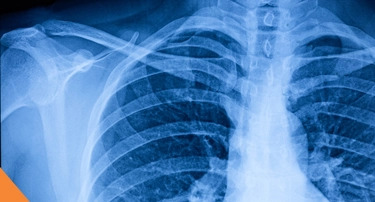

World Radiography Day 2025: Celebrating the Heroes Behind Medical Imaging

Human nature is such that we often ignore the real heroes behind every evolution that has helped humanity, and healthcare is no different.